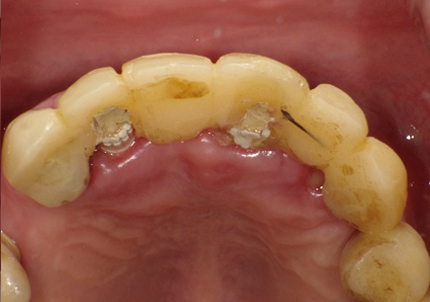

2.前装冠除去、メタルコア除去

3.サージカルガイド(インプラント埋入用)作製(2019年3月)